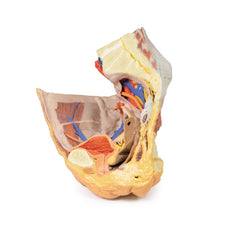

Lateral to these organs, branches of the internal iliac artery can be identified – as well as a retained median

sacral artery in the midline between the two common iliac arteries. On the left side only the uterine artery can

be seen laterally. On the right side, the obturator, superior vesical, and uterine arteries can be observed. In

addition, the origins of the inferior epigastric artery and vein can be seen arising from the external iliac

vessels just prior to exiting the inferior abdominal cavity.